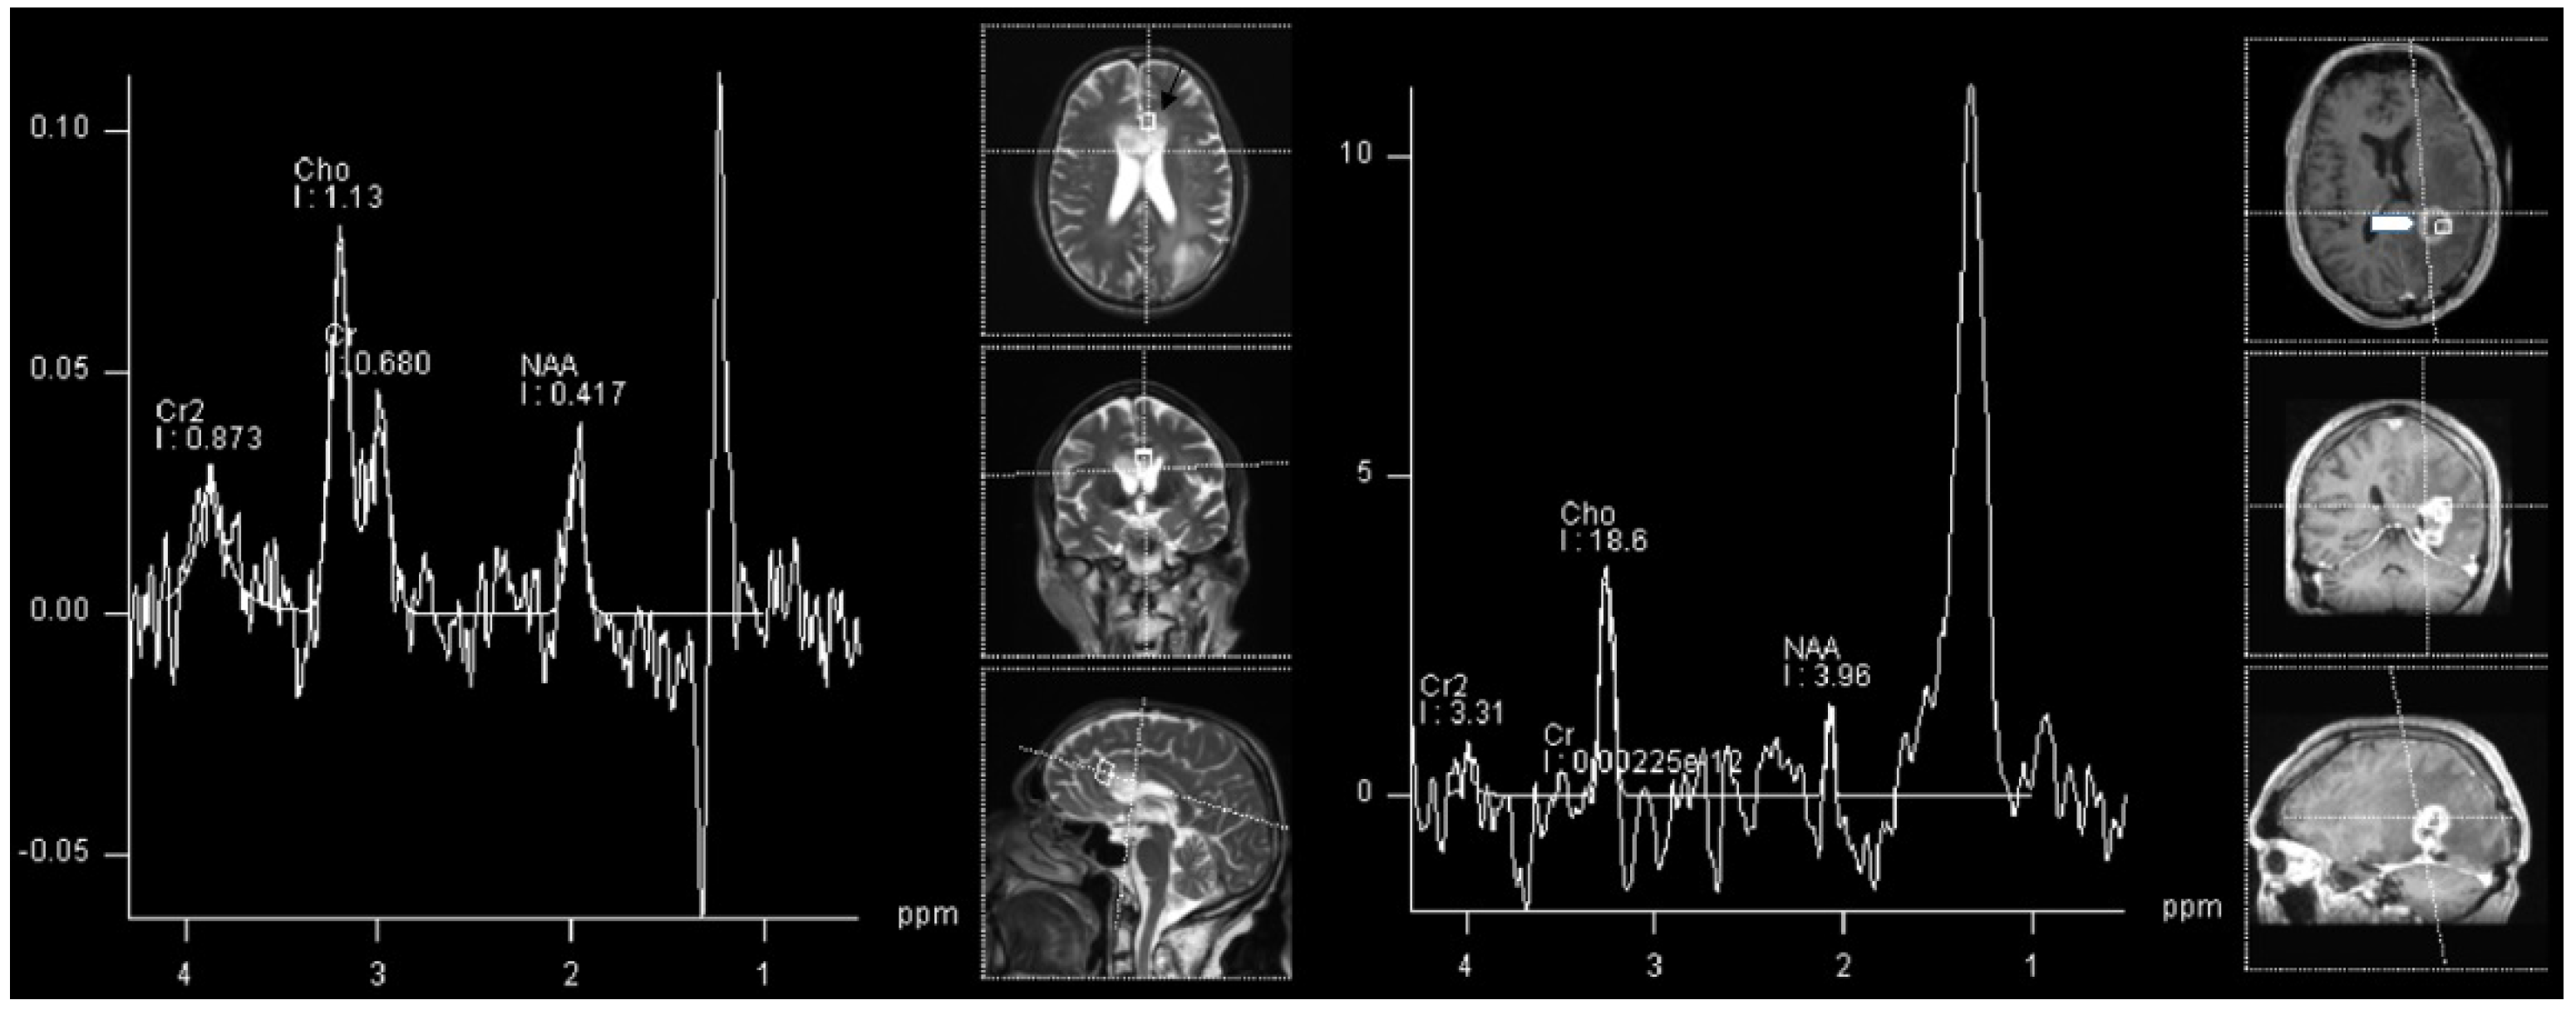

The most common glioma in the pediatric population is pilocytic astrocytoma [35]. This tumor type is not only the most common glioma, but is the most common brain tumor in children in general, accounting for around 15% of all brain tumors in this population [36]. The imaging of the pilocytic astrocytoma is fairly straightforward using regular structural MRI sequences, however, when performed, MRS show a high Cho/NAA and Cho/Cr ratio, and low Cr with a decreased NAA/Cr ratio [37]. These changes can be seen in an example of a 2 year old patient with histologically proven cerebellar pilocitic astrocytoma (Figure 1).

High-grade gliomas, not otherwise specified (NOS) are the most common high-grade gliomas in children [35]. There is not much difference in interpreting spectroscopy findings in children compared to those of adults. The best indicator of malignancy was found to be the NAA/Cho ratio. High-grade astrocytic tumors tend to have more decreased NAA and increased Cho compared to the lower-grade tumors [38]. However, as can be appreciated in our real-world example, relying solely on a spectroscopy can be misleading, especially in differentiating various diffuse tumors (as in our example in Figure 2), as both, lower and higher grade diffuse tumors can have similar spectra, albeit a difference between diffuse and circumscribed gliomas is usually clear (Figure 1 vs. Figure 2).

Figure 1. 1H-MRS in a patient (2 Y) with pilocitic astrocytoma (black arrow). Significantly increased Cho and decreased NAA and Cr are observed.

Figure 2. 1H-MRS in a patient (15 Y) with astrocytoma grade 3 (left, black arrow) and in a patient (8 Y) with astrocytoma WHO grade 2 (right, white arrowhead). Similar spectra are present in both grade 3 and grade 2 astrocytoma with increased Cho and decreased NAA, with the absence of Cr decrease.